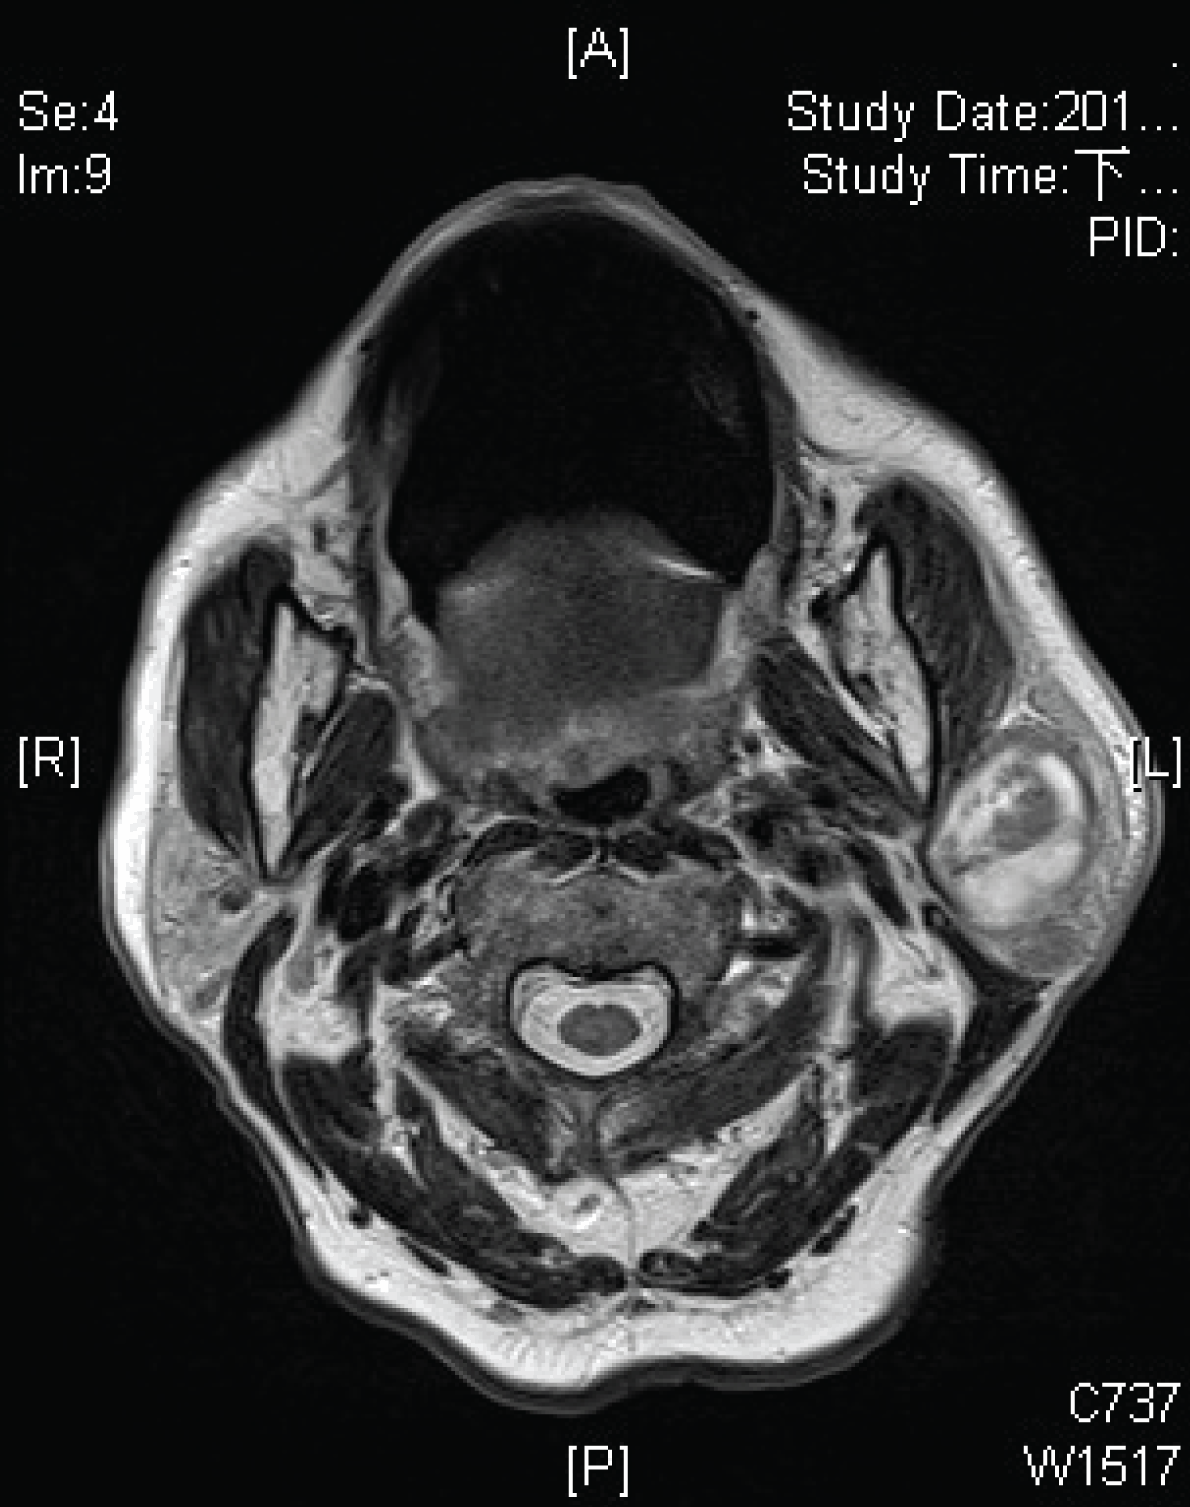

A 72-year-old man was presented to our clinic with a left cheek swelling mass with mild tenderness for one month. He was a heavy smoker with at least two packs of tobacco per day. Clinically, the tumor was located inferior to the left auricle; with elastic, tactile, movable content, and was well capsulated. No other palpable neck mass or facial palsy was noted, and there were no overlying skin changes suggestive of parotiditis. An oral cavity examination revealed no abnormal findings. A flexible nasopharyngoscopic examination revealed negative pathological findings of the nasopharynx, oropharynx, hypopharynx, and larynx. Head and neck T2-weighted MRI scan showed a 3x3.7 cm high intensity mass within the left superficial parotid gland. Small cervical lymphadenopathies were also apparent in bilateral level II and I. In T2-weighted image, left parotid high signal with central necrosis suggestive of left pleomorphic adenoma or mixed tumor. (Figure 1) In T1-weighted image post contrast infusion, left well demarcated parotid mass was moderated enhanced, with some low to moderate signal and heterogenous material inside. Highly suggestive of tumor central bleeding or granulomatous disease. (Figure 2) In T2-weighted image, left parotid tumor shows high signal with central necrosis, suggestive of granulomatous disease. (Figure 3)

Figure 2: In T1-weighted image post contrast infusion, left well demarcated parotid mass was moderated enhanced, with some low to moderate signal and heterogenous material inside. Highly suggestive of tumor central bleeding or granulomatous disease.

Figure 3: In T2-weighted image, left parotid tumor showing high signal with central necrosis, suggestive of granulomatous disease.